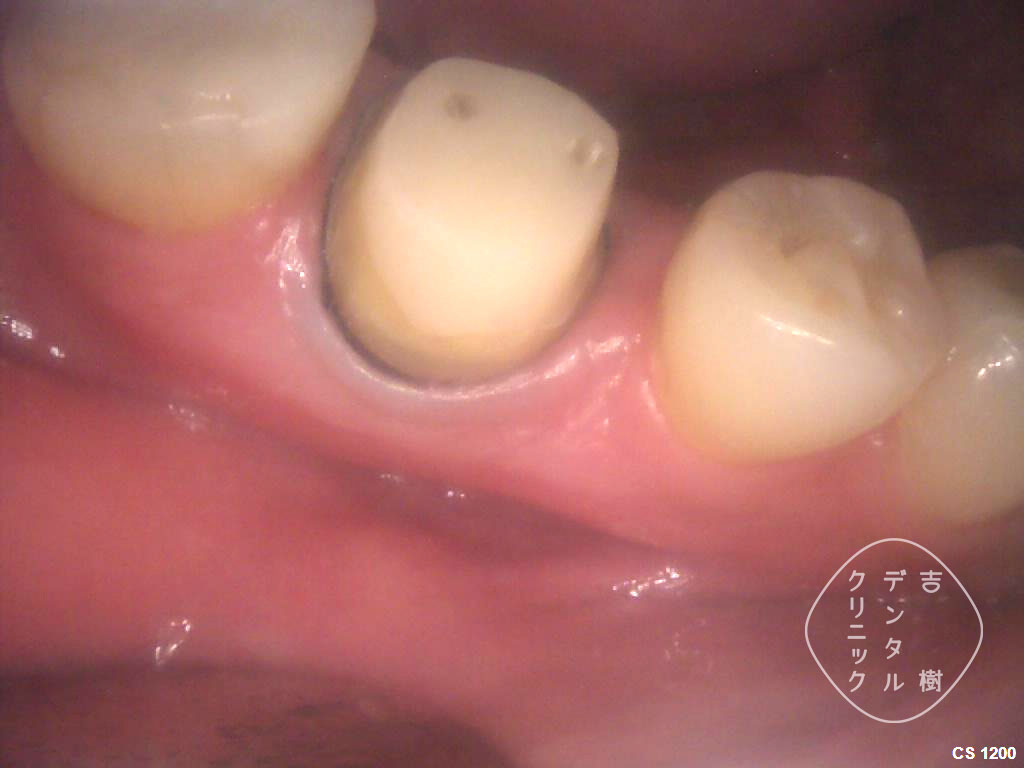

エクストルージョンは、歯の根を引き出して被せ物を取り付ける治療法でした。これに対して、「クラウンレングスニング」では、外科的に歯肉や骨を切除して歯の根を外に出し、被せ物を取り付けます。

クラウンレングスニングのメリットとして、エクストルージョンに比べて治療期間が短いことがあります。しかし、歯肉や骨を切除するため、この治療が行える歯の場所には制限があります。

①虫歯で崩壊してしまった奥歯

②「歯冠延長手術」で歯肉を切除した

③「歯冠延長手術」で歯肉を切除した

④歯を修復し、土台を作る治療をする

⑤被せ物を装着し、治療完了